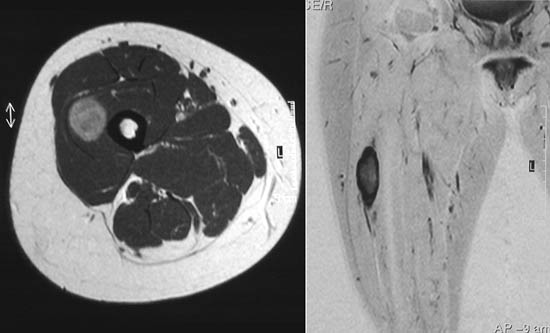

| The subcutaneous masses seen above with a head CT scan at the level of the maxilla and at the level of the jaw are neurofibromas in a patient with neurofibromatosis type I (von Recklinghausen disease). Another neurofibroma appears in the thigh region as seen with MRI scan below (axial T1 on the left; coronal STIR on the right). NF1 is an autosomal dominant condition. Half of cases result from new mutations in the NF-1 gene on chromosome 17 which encodes for a protein that is a negative regulator of the ras oncoprotein. Overactivity of ras leads to neoplasia, specifically development of neurofibromas in nerves and dermis anywhere in the body. |